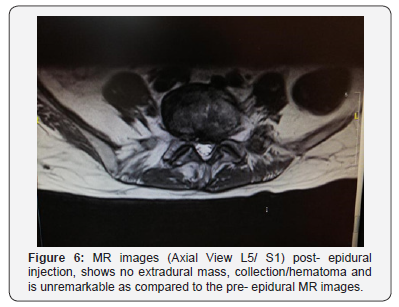

Her symptoms however continued to persist even after 24 hours to which an MRI was done to rule out epidural hematoma formation. The MRI reveals no extradural mass or hematoma collection. It was unremarkable as compared to the pre- epiduralinjection MR images (Figure 4-6). All other blood investigations and imaging was also normal. She subsequently underwent an emergency laminectomy of the L4/L5 and L5/S1 level after 6 days of observation for spontaneous neurological recovery. Intraoperative findings reveal no hematoma and upon laminectomy, the dura bulge outwards (Figure 7).